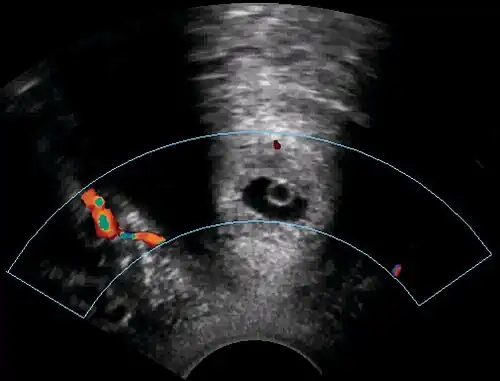

A woman in her 20s came to the gynecologic clinic because of a positive pregnancy test and a history of a previous ectopic pregnancy. The vaginal ultrasonography performed by Dr. Jesper Agrell showed a gestational sac in the cervix as displayed in the sagittal plane. The corpus of the uterus is located at right in the image. There was a discernible heartbeat, and the gestational sac diameter corresponded to a gestational age of 5 weeks. The distance from the gestational sac to the external orifice was only 15 millimeters.